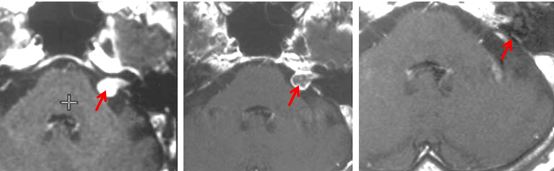

Trường hợp 1: Bệnh nhân Lê Văn C, nam, 71 tuổi. Được chẩn đoán là u dây thần kinh số VIII với triệu chứng ban đầu là đau đầu, ù tai. Bệnh nhân có tiền sử bệnh tim nên không còn chỉ định phẫu thuật mổ mở. Bệnh nhân được xạ phẫu bằng dao gamma quay với liều 14Gy. Sau xạ phẫu 6 tháng, về lâm sàng: hết đau đầu và ù tai, không có triệu chứng liệt mặt.

Trước điều trị:  u dây VIII bên phải có kích thước 2cm

Sau xạ phẫu 6 tháng: u nhỏ hơn về kích thước và có hoại tử trong u

Hình 2. Hình ảnh MRI u dây thần kinh số VIII trước và sau xạ phẫu bằng dao gamma quay